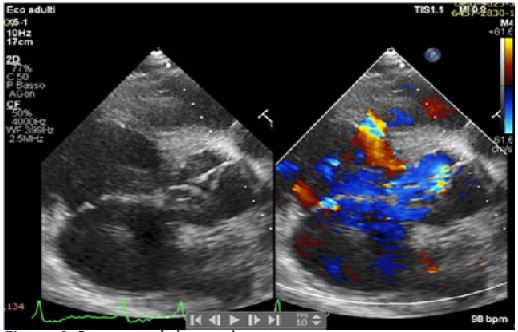

A 42-years old Senegalese man was referred to our department for dyspnea on exertion (NYHA II-III) and clinical signs of heart failure. In his clinical history an undefined cardiopathy, known since childhood but not investigated because asymptomatic, was reported. General examination revealed tachyarrhythmic pulse (rate of 103 per minute) along with normal blood pressure (130/65 mmHg) and arterial oxygen saturation (SpO2 97-99%). Electrocardiography demonstrated atrial fibrillation with left ventricular hypertrophy and signs of pressure overload (Figure 1), while chest X-Ray showed severe cardiomegaly and pulmonary congestion. Transthoracic Echocardiogram (TTE) with color Doppler revealed the presence of a 21 mm perimembranosus Ventricular Septal Defect (VSD), below the aortic valve, with relevant left-to-right shunt (gradient 90 mmHg), partially closed by prolapsing right coronary cusp and accessory tricuspid valve tissue (Figures 2 and 3). A hypertrophied muscle bundle in the mid-ventricular region of the Right Ventricle (RV) along with color-flow turbulence was documented (Figure 4). Due to misalignment, no accurate estimation of intraventricular RV pressure was feasible, but moderate tricuspid regurgitation revealed an atrioventricular gradient of 70 mmHg, suggesting high RV pressures. Other findings were severe aortic valve regurgitation with severe dilation of ascending aorta (diameters of sinuses of Valsalva 60 mm, 28 mm/m2, z-score +6,3, tubular ascending aorta 48 mm, 23 mm/m2, z-score +5,7). 2D and 3 D Transoesophageal Echocardiographic Examination (TOE) confirmed the presence of the anomalous muscle band dividing the RV into two parts: a high-pressure inlet portion and a lower pressure outlet portion (Figures 5 and 6). Severe dilation of both aorta and pulmonary trunk was revealed, confirming severe aortic valve regurgitation with multiple jets and determined by different factors (lack of coaptation, prolapse of the right cusp and distortion of the noncoronary cusp). To accurately measure RV pressures cardiac catheterization was performed. The systolic pressure of the right ventricular inlet and the outlet pressure were 78 and 38 mmHg respectively, determing an intraventricular gradient of 40 mmHg. There was no pressure gradient between the right ventricle outlet tract and the main pulmonary artery (systolic/diastolic/mean pressures were 38/18/25 mmHg respectively). Normal coronary arteries were documented. Patient was scheduled for corrective surgery in the form of resection of the anomalous muscle bundle along with patch closure of the VSD and Bentall procedure for ascending aorta or aortic valve replacement.

Figure 4: Parasternal short axis.